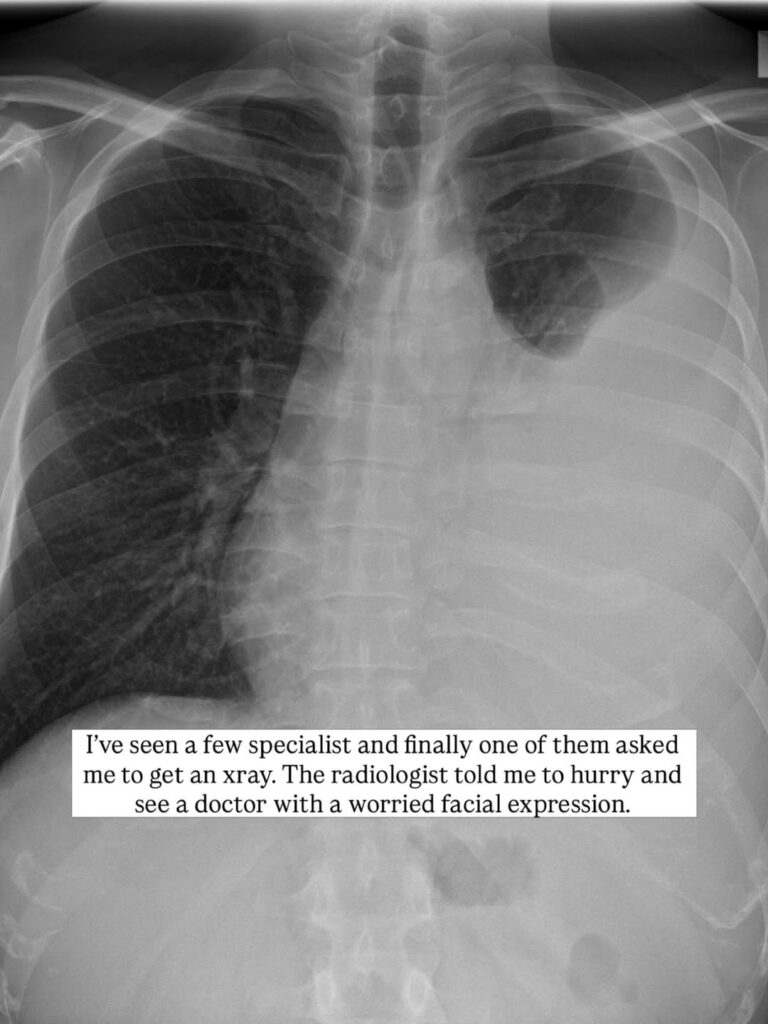

Concerned about his persistent cough, he sought medical attention and underwent a chest X-ray.

"The radiologist told me to hurry and see a doctor with a worried expression. After seeing my X-ray, the doctor said my entire left lung was infected and filled with water, causing a part of it to collapse. They said it could be cancer or TB — and asked me to pray it was TB," he recounted.